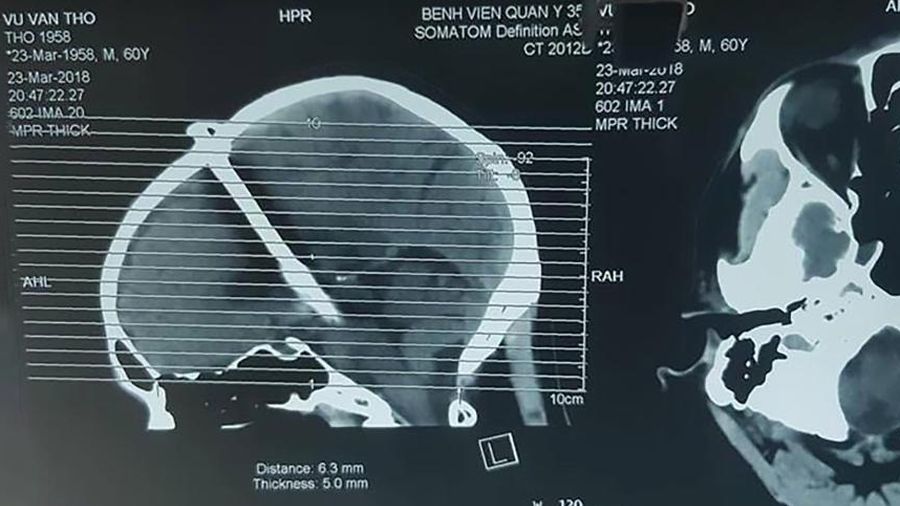

60-letni Vu Van Tho po urodzinowym przyjęciu nie czuł się najlepiej. Mimo silnego bólu głowy mężczyzna zwlekał z udaniem się po pomoc aż 48 godzin. Jak się okazało, przez cały czas miał w czaszce niemal 8-centymetrowy gwóźdź.

Prawdziwą skalę urazu obrażeń dopiero prześwietlenie. Wtedy okazało się, że gwóźdź ma prawie 8 centymetrów. Zdjęcia mężczyzny zamieścił w sieci doktor Le Hoang Anh z Wojskowego Szpitala 354 w wietnamskim Hanoi. To właśnie on był jednym z lekarzy, którzy zajęli się nietypowym pacjentem.